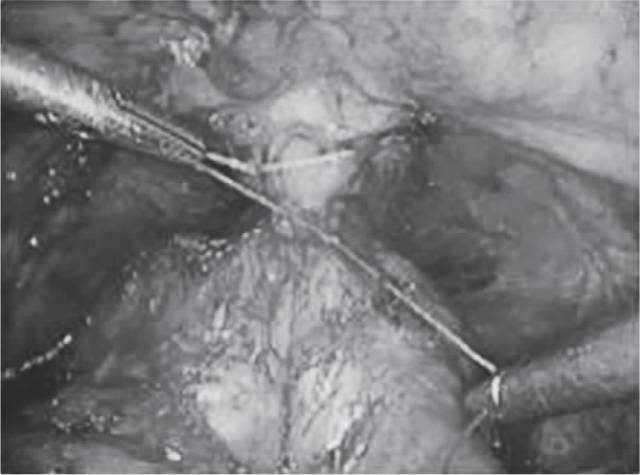

1983年Walsh首次提出前列腺癌(PC)的外科治疗,包括根治性前列腺切除术(RP),该手术涉及在尿道和膀胱之间的整个前列腺腺体切除、双侧精囊切除以及周围组织的充分切除以达到切缘呈阴性(图1和图2)。同时行双侧盆腔淋巴结清扫术。不论任何途径(耻骨后开放,经会阴、腹腔镜、机器人辅助)的RP目标都是达到病灶根治,同时保护尿控和可能的勃起功能。自从Walsh首次介绍了保留神经的解剖性耻骨后途径前列腺根治性切除手术以来,这种方法便成为局灶性PC手术的金标准,并且应用广泛。

图2 前列腺切除后的前列腺床